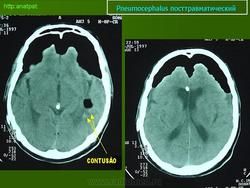

El siguiente caso corresponde a un traumatismo craneoencefálico grave, con fractura de los huesos de la base del cráneo (se observa "hemosinus" postraumático en el seno esfenoidal y en las celdillas etmoidales) y del hueso temporal izquierdo. A través de las fracturas de la base de cráneo han penetrado numerosas burbujas de aire que han difundido por el espacio subaracnoideo de las cisternas basales y de los surcos. El neumocéfalo no es muy llamativo porque se ha producido edema cerebral difuso. El parénquima encefálico ha aumentado de volumen y no ha dejado espacio libre en la cavidad intracraneal (Figuras 1, 2, 3, 4 y 5).

FIGURA 1

FIGURA 2

FIGURA 3

FIGURA 4

FIGURA 5